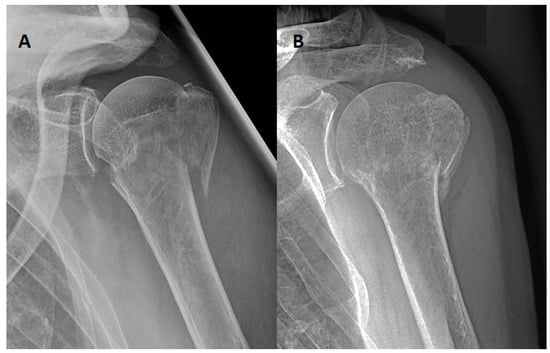

Furthermore, we will describe two individual cases in more detail. A 72-year-old man from group [C] who suffered an AO 11-B2 fracture reported severe discomfort as early as 48 h after receiving an abduction brace. Contrary to the study protocol, a change was made to a simple sling for comfort reasons, which was tolerated for another 48 h before the patient decided to quit immobilisation. Nevertheless, fracture healing was satisfying; the CS after 6 weeks was above the average of 70 points (Figure 3).

Figure 3. Case of a 72-year-old man of group [C] with an AO 11-B2 fracture, (A) anteroposterior X-ray from the fracture day. Patient-related termination of orthosis protocol after 96 h. (B) Anteroposterior X-ray after 6 weeks with acceptable healing and CS above the average value of 70 points.